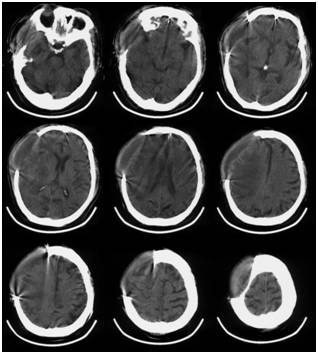

术后床旁移动CT复查头颅CT如Fig. 2所示,清除大部分血肿,少量血肿局部残留。复查血常规示:Hb104g/L,PLT50×109/L,HCT30.3%。给予脱水、抗感染、止血、神经保护、升血小板、营养支持等综合治疗,患者病情逐渐平稳。后出现肺部感染、上消化道出血等相关并发症,给予相应治疗后均好转。2017年2月16日右侧瞳孔对光反射恢复。2017年2月19日复查头颅CT示血肿基本吸收,中线结构无明显移位(Fig.3)。患者意识状态逐渐改善,于2月23日患者神志朦胧,可简单完成遵嘱动作。于2月27日出院,转当地医院康复治疗,出院一周后患者完全清醒,语言清,左侧偏瘫,左侧肢体肌力1-2级。

Fig.3术后19天复查头颅CT示血肿基本吸收